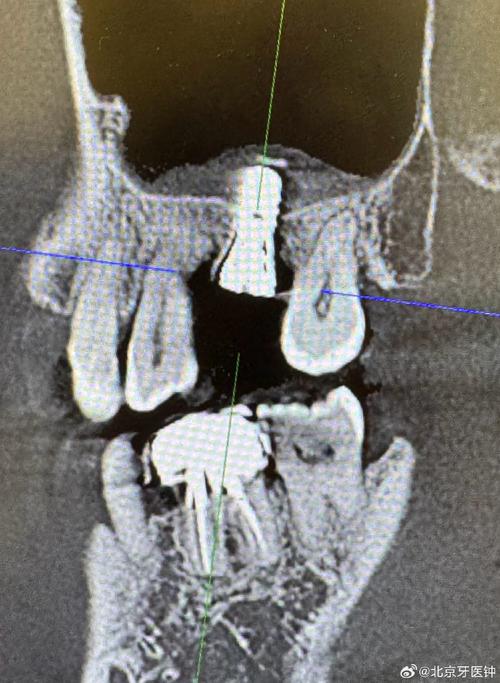

- 沟通很重要:如果你对手术过程有疑问或担忧,在手术前务必与你的医生充分沟通,医生会根据你的具体情况(拍CBCT片评估后)告知你计划采用哪种手术方式,并解释大致的操作过程、预期效果和潜在风险。